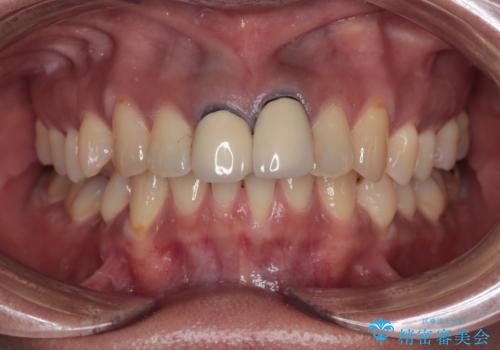

前歯の黒い縁が気になる オールセラミッククラウンで自然な口元に

- 前歯のクラウン付近の歯肉が黒く見えることを気にして来院された患者様です。

10年以上前に根管治療を行っており、その際にはラバーダムを使用してしっかりと治療を行っていたとのことで、今回は根管治療は行わずに土台のみを作り替えた上で、オールセラミッククラウンにて補綴治療を行うこととしました。

オールセラミッククラウンは金属を使用していないため、本物の歯のような綺麗な仕上がりとなりました。